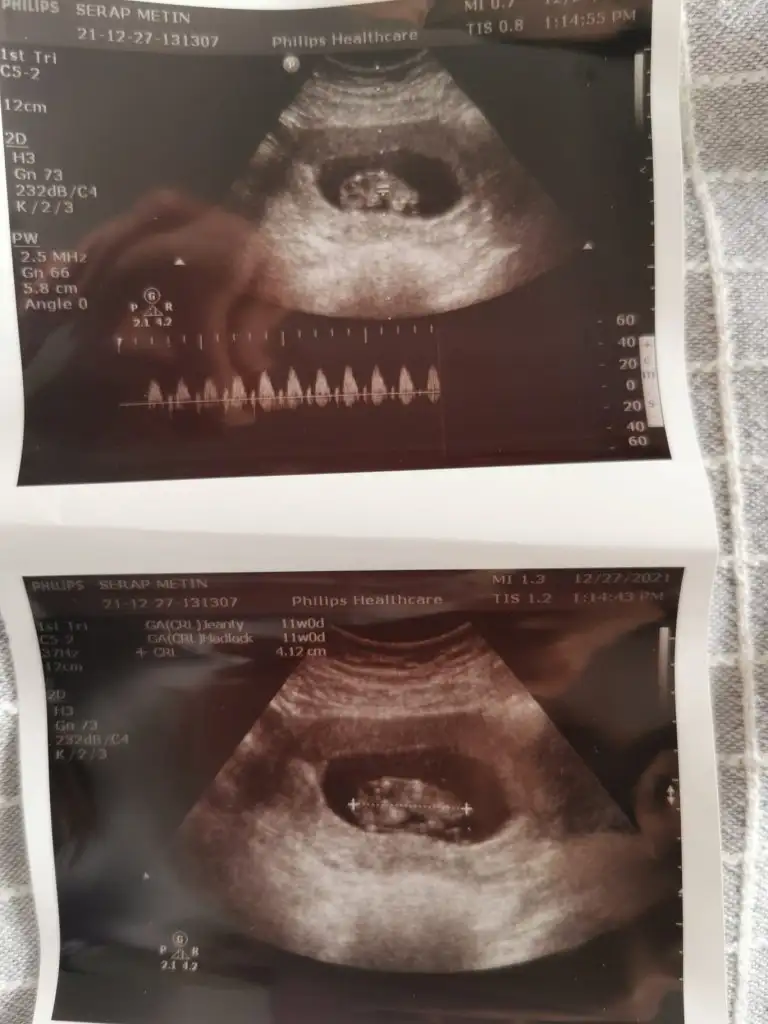

Merhaba,

Ikra meyra bir bakabilir misin. Kardeşim için 11 haftalık. Şimdiden teşekkürler.

Eklentiler

• IMG-20211227-WA0004.webp

30,5 KB · Görüntüleme: 53

• IMG-20211227-WA0008.webp

31,5 KB · Görüntüleme: 61

• IMG-20211227-WA0005.webp

17,5 KB · Görüntüleme: 55